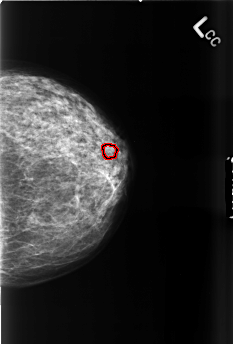

FILE: B_3460_1.LEFT_CC.OVERLAY

TOTAL_ABNORMALITIES 1

ABNORMALITY 1

LESION_TYPE CALCIFICATION TYPE PUNCTATE-PLEOMORPHIC DISTRIBUTION CLUSTERED

ASSESSMENT 4

SUBTLETY 3

PATHOLOGY BENIGN

TOTAL_OUTLINES 1

BOUNDARY